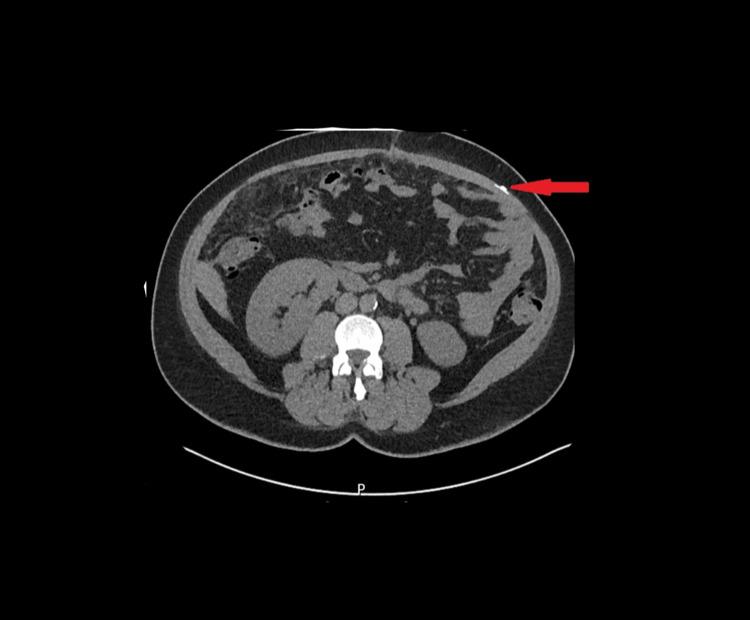

Midline laparotomy remains essential in gynecological oncology, and rectus sheath catheters (RSCs) are commonly used for postoperative analgesia. We report the case of a 46-year-old woman who underwent midline laparotomy for a suspected ovarian mass, which intraoperatively revealed mucinous ascites consistent with pseudomyxoma peritonei. An RSC was placed for pain control; however, during removal, a 5 cm segment remained embedded in the subrectus sheath. Initial imaging with plain X-ray failed to detect the retained catheter, which was eventually confirmed by computed tomography (CT). Intraoperative localization attempts using C-arm fluoroscopy and palpation were unsuccessful. A novel adjunctive approach using a Flir One Pro smartphone-based thermal camera (Flir One Pro Systems, Sweden), approved by clinical governance and operated by a trained surgeon, successfully identified localized heat on the abdominal wall, corresponding to inflammation caused by the retained catheter. Guided by this finding, a 2 cm incision was made to retrieve the coiled catheter without complications. The patient recovered well and was discharged on the third postoperative day. Histopathology confirmed pseudomyxoma peritonei, and the case was referred to a colorectal multidisciplinary team. This report highlights the feasibility and clinical value of thermal imaging as a radiation-free, real-time adjunct for detecting retained surgical materials, particularly when conventional imaging fails. Thermal imaging offers portability, precision, and safety, though its broader adoption requires standardized training, validation, and further research.

中线剖腹术在妇科肿瘤学中仍然至关重要,腹直肌鞘导管(RSCs)常用于术后镇痛。我们报告了一例46岁女性的病例,该患者因疑似卵巢肿块接受了中线剖腹术,术中发现黏液性腹水,符合腹膜假黏液瘤。放置了一根RSC用于控制疼痛;然而,在拔除过程中,一段5厘米长的导管仍嵌在腹直肌鞘内。最初的X线平片成像未能检测到残留导管,最终通过计算机断层扫描(CT)得以证实。使用C形臂荧光透视和触诊进行术中定位的尝试均未成功。一种新颖的辅助方法,使用经临床管理部门批准、由训练有素的外科医生操作的基于Flir One Pro智能手机的热成像相机(瑞典Flir One Pro系统公司),成功在腹壁上识别出局部发热,对应于残留导管引起的炎症。在此发现的引导下,做了一个2厘米的切口取出盘绕的导管,未出现并发症。患者恢复良好,术后第三天出院。组织病理学证实为腹膜假黏液瘤,该病例被转诊至结直肠多学科团队。本报告强调了热成像作为一种无辐射、实时辅助手段检测残留手术材料的可行性和临床价值,特别是在传统成像失败时。热成像具有便携性、精确性和安全性,不过其更广泛的应用需要标准化培训、验证和进一步研究。